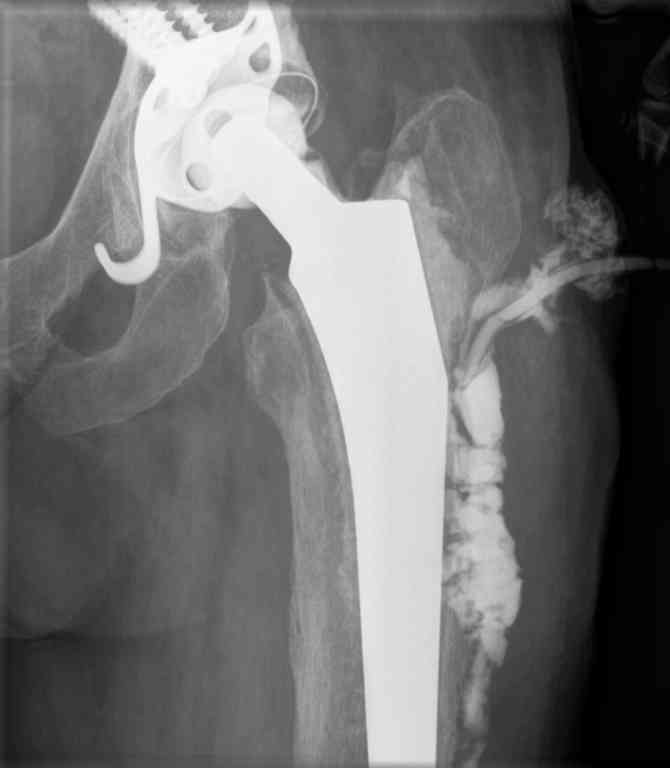

Уважаемые коллеги.Подскажите, пожалуйста, варианты ревизии у пациентки 65 лет с нагноением эндопротеза т\б сустава. В 2004 году установлен эндопротез с гладким п\о течением и заживлением раны. На протяжении всего времени больную беспокоили боли в области паха: бедра. Поступила с обстрением болевого синдрома и уже в отделении развился покожный абсцесс с формированием свища. Фистулография- в приложении. Достаточно ли удалить протез и установить промывную систему или лучше спейсер? Если спейсер, тогда как дренировать костномозговой канал? Спасибо.

Евгений, судя по снимкам и анамнезу пациентке был установлен тотальный цементный эндопротез: ножка Мюллера прямая, кольцо Ганса, на 4-х винтах,

чаша на цемент, головка - керамическая. Произведено либо Матис либо Centerpulce (сегодня Зиммер). Гладко никогда похоже не было - инфекция

сидела в бедренном канале и разрешилась формированием свища, опять таки судя

по снимкам - идущего не в полость (не факт) сустава а в бедренный канал.

Ножка явно нестабильна. В таком случае вряд ли обойдется одноэтапной ревизией. Я бы определился с микробом - подготовил антибактериальную

программу и антисептики - выполнил хорошую ревизию сустава: убрал ногу и голову 100%, санировал бедренный канал и фрезами тоже, убрал бы 1/3 пробки (если она из кости) и всю (если она полимерная), тазовый компонент при стабильности может и оставил! (зависит от местных находок и вирулентности заразы), а может быть убрал только чашу и цемент (варианты разные), установил бы спейсер с антибиотиками (флора уже известна) с моделированием головки под 28 мм (если чашу оставил) и больше если удалил только чашу, и

еще больше (если удалил кольцо) - костномозговой канал дренировать не надо (но спейсер должен заполнить все свободное пространство (в качестве мерила используйте удаленную ногу с цементом или рашпиль последний). Дренировал бы только мягкотканную рану (полость сустава) активным дренажом и недолго.

Затем классическое ведение 3-4 месяцев спейсер и вторая ревизия с бактериоскопией из разных мест и установка новых компонентов - лучше бесцементных, или вновь спейсер на следующий срок. Все долго, дорого и нудно, но другого не дано. С уважением и удачи в трудной работе.